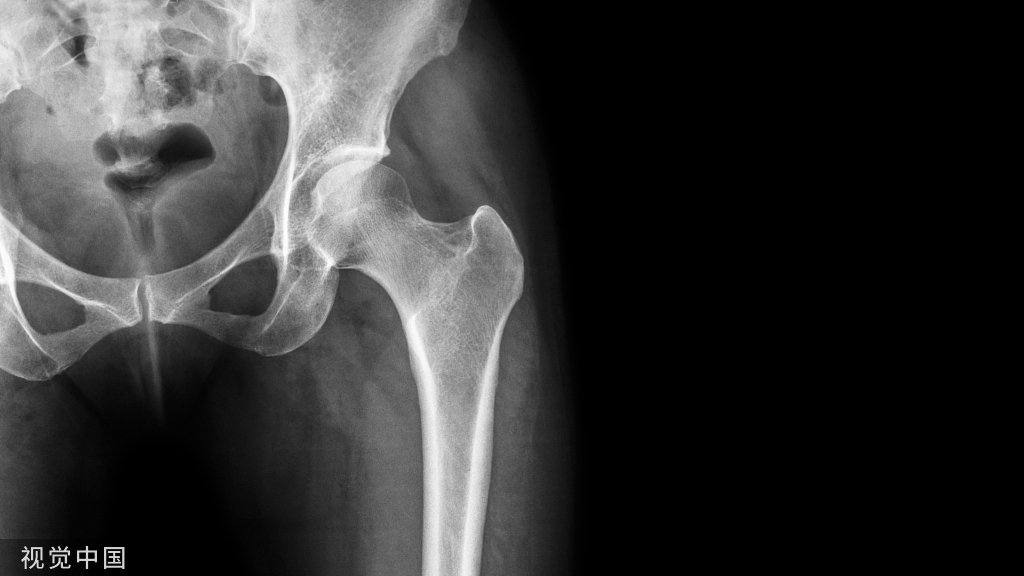

关节镜诊疗髋关节疾病具有对关节血运和稳定性破坏小的优势, 对于减轻疼痛、改善关节活动功能、延缓关节置换的时间也具有积极的作用。然而,髋关节镜是一种技术要求苛刻的手术,因为股骨头的球面形状及致密的关节囊和肌肉组织包绕着髋关节。

关节镜诊疗髋关节疾病具有对关节血运和稳定性破坏小的优势, 对于减轻疼痛、改善关节活动功能、延缓关节置换的时间也具有积极的作用。然而,髋关节镜是一种技术要求苛刻的手术,因为股骨头的球面形状及致密的关节囊和肌肉组织包绕着髋关节。髋关节镜能够进入髋关节中央间室和外周间室。中央间室包括股骨头和髋臼关节面,盂唇和圆韧带。外周间室包括股骨颈和周围关节囊及滑膜。